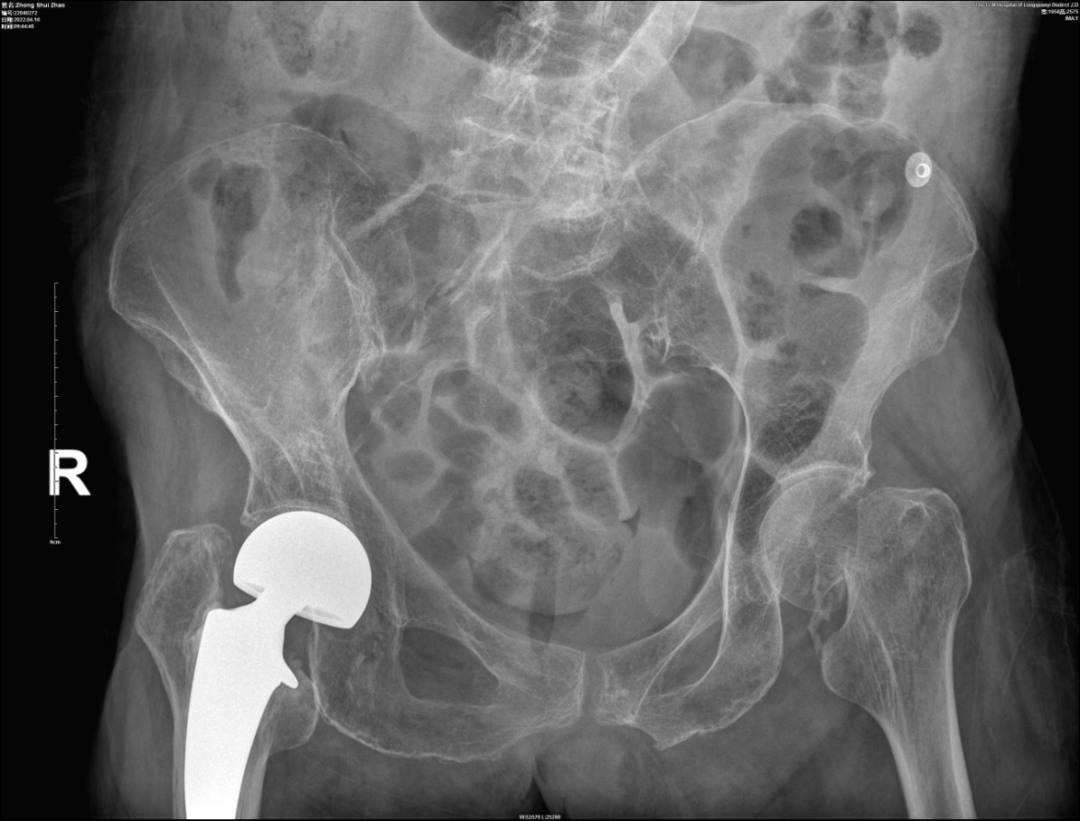

术前X片

入院后,通过详细的查体及相关辅助检查,钟奶奶被诊断为“1.左股骨颈骨折GardenⅢ型 2.高血压性心脏病 3.中度贫血 4.肺部感染5.室性早搏合并二联律 6.电解质代谢紊乱 7.乙肝病毒携带者 8.骨质疏松症 ”。

据了解,钟奶奶10+年前曾因右侧股骨颈骨折,在我院骨伤科行右侧人工半髋关节置换术,手术非常成功,不幸的是钟奶奶这次又因摔伤导致左侧股骨颈骨折。然而,这次住院钟奶奶已经101岁高龄,合并多种内科疾病,身体状况大不如十年前,手术风险很大。